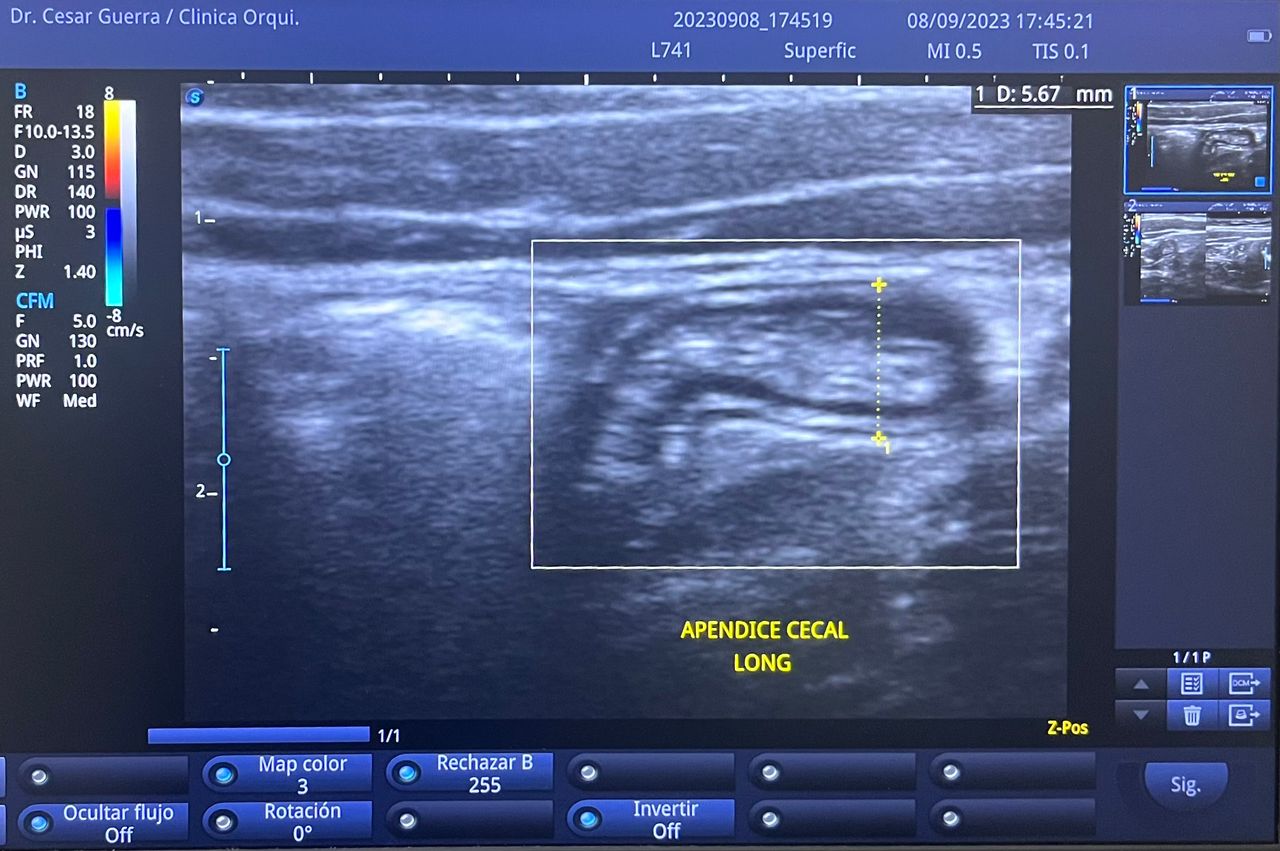

Médico general con 15 años de experiencia, master en enfermedades infecciosas y antibioticoterapia por parte de la Universidad Cardenal Herrera en Valencia, ademas de diversos diplomados en el área de Infectología y Parasitología, Urgencias, Imagenología y Medicina del Trabajo. He laborado en Hospitales y Clínicas en el área de Urgencias, en Laboratorios realizando estudios de Imagen, en especifico ultrasonidos de todo tipo desde básicos hasta avanzados incluidos los obstétricos estructurales, en Secretaría de Salud del Estado de Querétaro realizando ultrasonidos obstétricos para la detección de malformaciones en los tres trimestres del embarazo en diversos centros de salud, como médico de Empresas en el campo de Salud Laboral y actualmente en este consultorio en donde para su mejor atención y siempre buscando integrar la mayoría de las herramientas diagnosticas cuento con equipo de ultrasonido como apoyo en la exploración del paciente o como servicio diagnostico por imagen, realizo ultrasonidos convencionales (hepatobiliar (hígado, páncreas, vesícula y bazo), vías urinarias, ginecológico abdominal y transvaginal, tiroideo, prostático, testicular, pared abdominal) y especializados (dopler obstétrico en los 3 trimestres de embarazo), musculoesquelético en lesiones deportivas. También cuento con un equipo de electrocardiograma de 12 derivaciones para monitoreo completo del funcionamiento cardiaco, espirometria para evaluar la función pulmonar en la consulta, pruebas rápidas que se realizan en consultorio para detectar de forma mas precisa enfermedades infecciosas como Influenza A y B, covid19, infecciones urinarias, dengue, zika, chikungunya. Cuento con diversas vacunas para prevención de enfermedades. Siempre con el objetivo de dar el mejor servicio y atención a su salud. Lo espero en consulta para escucharlo y estudiar su caso de la forma más completa posible, estoy seguro de que tendremos las mejores opciones para su tratamiento. Mi tranquilidad es que usted se vaya con todas sus preguntas e inquietudes resueltas.